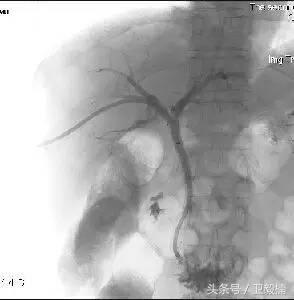

一、全身各部位血管造影;